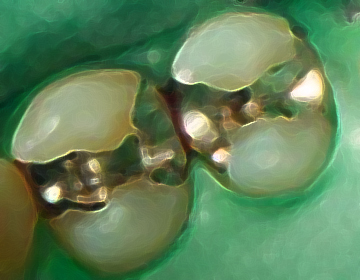

修復治療では、虫歯を徹底的に除去し、噛み合わせを安定させ、

噛めるという実感を追求した材料で、確実な虫歯治療を行います。

麻酔後、ラバーダム防湿を行い、治療部位を分離します。

ルーペを用いて修復物を除去します。

術野を十分の明示、乾燥させてからカリエスチェッカー(齲蝕検知液)で虫歯を染め出します。

虫歯を完全に除去、深い虫歯にはMTA(覆罩剤※)で神経を保護します。

痛み、レントゲン検査による治療結果の判定。

直接修復剤は研磨等の仕上げ、型取りしたものを装着します。